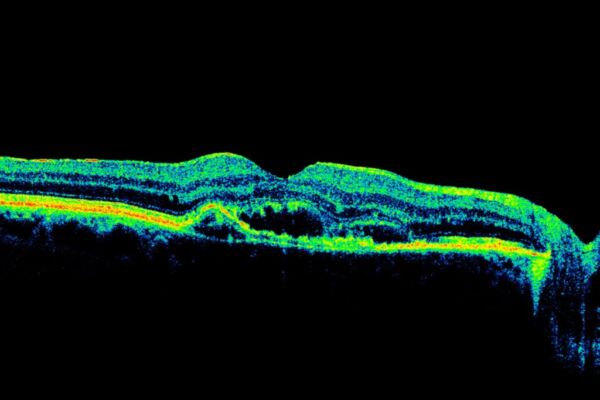

- optiline koherentne tomograafia (OCT) – uuring võimaldab näidata võrkkesta erinevaid kihte, et arst saaks hinnata, kas koevedelik on kogunenud maakuli sisse (joonised 1 ja 2). OCT annab väga täpse ülevaate võrkkesta väikseimatest struktuuridest ja seda saab kasutada ka ravi edukuse jälgimiseks.

Joonis 2: Diabeetilise maakuli tursega silmapõhi koos vedeliku kogunemisega maakuli all olevatesse kudedesse (tumedatesse piirkondadesse). Võrkkesta kihid on ebakorrapärased ja välja ulatuvad.